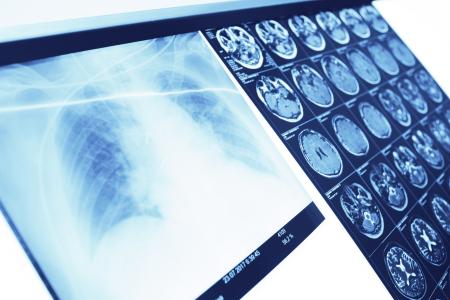

C'est une approche qui permet de lutter efficacement contre le syndrome de détresse respiratoire aiguë (SDRA) chez les patients plus âgés (Visuel Adobe Stock 175074485)

C’est une approche génétique prometteuses pour réparer les lésions pulmonaires mortelles dues au COVID-19, à la pneumonie, à la grippe ou encore à la septicémie chez les personnes âgées, que nous décrit cette équipe de l’Hôpital pour enfants Ann & Robert H. Lurie de Chicago. Une approche qui permet de lutter efficacement contre le syndrome de détresse respiratoire aiguë (SDRA) chez les patients plus âgés alors qu’il n’existe actuellement aucun traitement pharmacologique ou thérapie cellulaire.